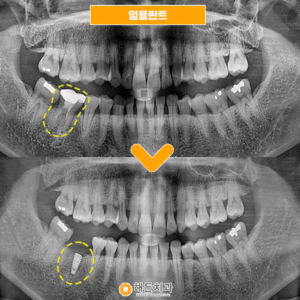

임플란트 환자분의 간식선물🍩

안녕하세요~ 해든치과입니다🤭   해든치과에는 가족단위의 환자분들이 굉장히 많으신데요!   임플란트 치료를 마무리하신 환자분께서 치료 잘 해주셔서 감사하시다며 다음에 올때 꼭 빵 사다주신다고 하셔서 빈손으로 오셔도 괜찮으니 그냥 오시라고 말씀드렸었는데       어머님 진료예약에 같이 내원해주시는길에 간식을 사다주셨습니다😭       항상 생각해주셔서 감사합니다 맛있게 먹고 힘내서 즐겁게 더보기…